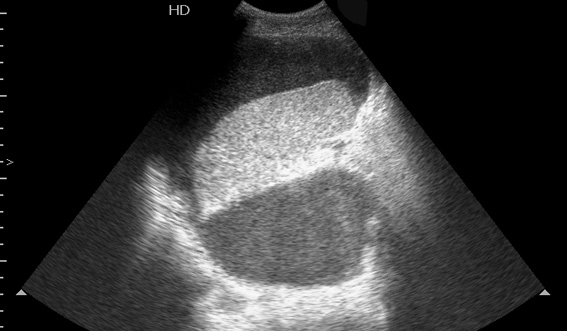

Мужчина средних лет, страдающий хроническим панкреатитом.

Температура 38-39 град, симптомы интоксикации, невыраженная боль в левом боку.

При УЗИ в области ворот селезенки/хвоста панкреас определяется жидкостное образование, переходящее в поддиафрагмальное пространство и заполненное акустически непрозрачной, мутной жидкостью.

Сонограмма селезенки. Продольное сканирование из левого бокового доступа.

Образование задренировано, получена гнойная жидкость с геморрагическим компонентом.

Завтра будет готов результат биохимии (амилаза) жидкости.